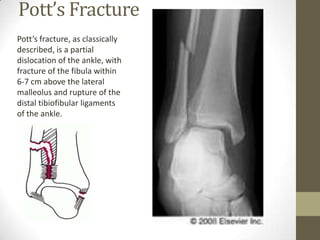

Pott’s Fracture

Pott’s fracture, as classically

described, is a partial

dislocation of the ankle, with

fracture of the fibula within

6-7 cm above the lateral

malleolus and rupture of the

distal tibiofibular ligaments

of the ankle.